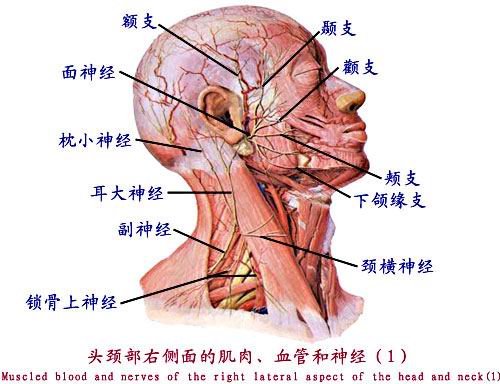

1. 1. 颈丛 Cervical plexus

由第1~4颈神经前支组成。 By 1-4 before the first cervical nerve branch components. 位于胸锁乳突肌深面。 Located deep to sternocleidomastoid. 主要分支有: The main branches are:

(1)浅支:为数条细小分支,自胸锁乳突肌后缘中点穿出,呈放射状分布于颈侧部、头后外侧、耳廓及肩部皮肤。 (1) superficial branch: several pieces small branches, since the sternocleidomastoid edge midpoint piercing, radial distribution in lateral part, the outer rear head, ear and shoulder skin.